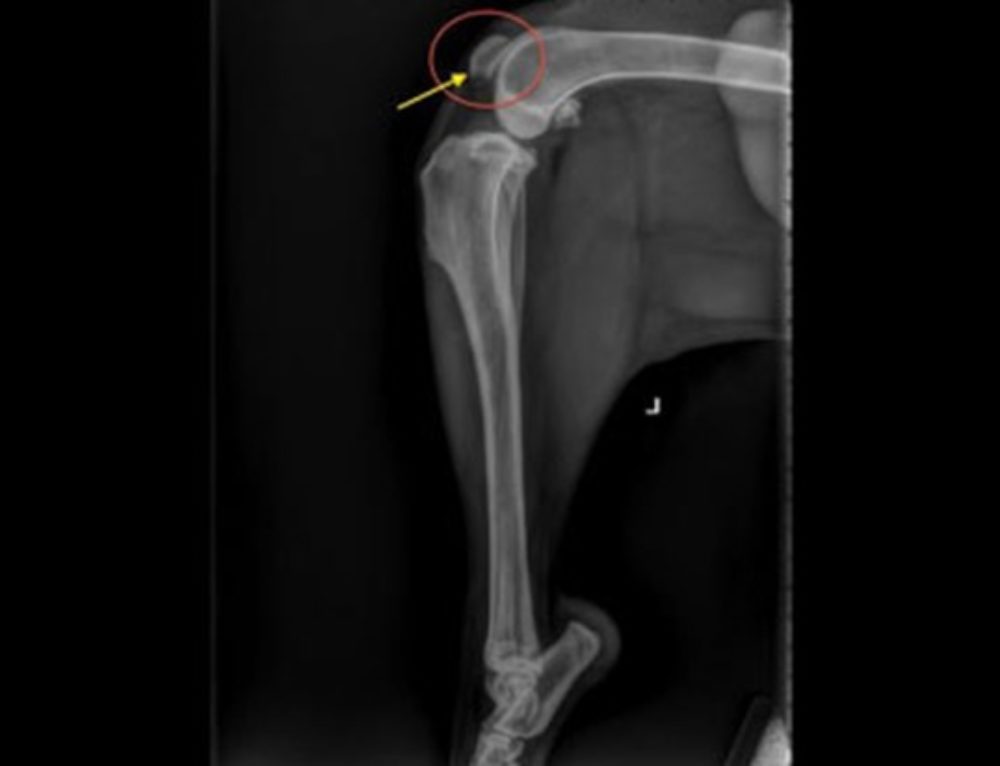

From www.vetlessons.com

FELINE LAMENESS — VETLESSONS Floating Kneecap Cat A luxating patella in your cat can be the result of. Patellar luxation is marked by four grades with grade 4 indicating the most severe condition of a dislocated kneecap. Luxating patella, the technical term for a kneecap popping out of place, creates instability in a cat's hind leg by reducing the functionality of the knee joint. Symptoms, causes, breeds. Floating Kneecap Cat.